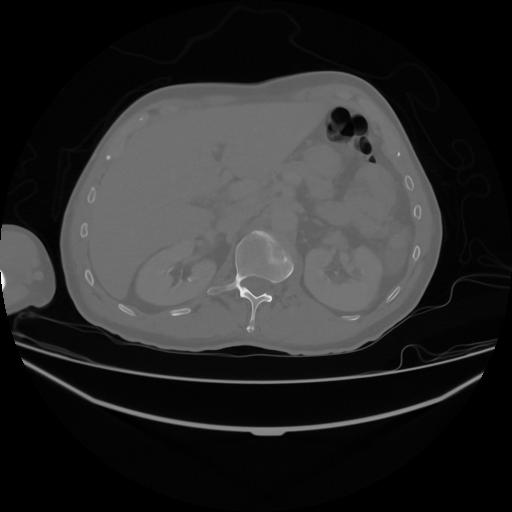

5 CUERPO,CE,Vol,1.0,CUERPO,,